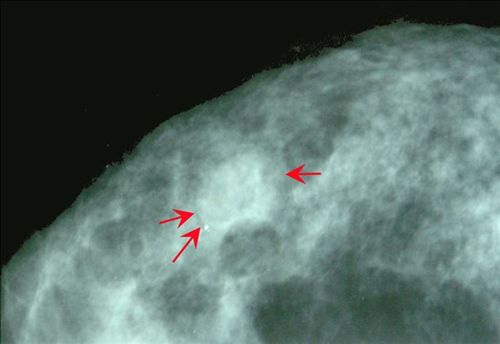

左乳腺纤维腺瘤-X线

影像表现:钼靶X线显示乳腺病灶周围有部分狭窄而等宽的放射透亮环(↑)

影像诊断:左乳腺纤维腺瘤(晕征)。